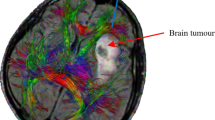

The most common brain malignant tumours, glioblastomas multiforme (GBMs), leave patients a median overall survival rate ranging from 12 to 18 months, as reported in Mehta et al. (2015). Moreover, despite affecting only 6 in 100,000 people, the treatment cost in Europe in 2010 was about 5.2 billion Euro (Olesen et al. 2012). Conventional treatment options such as surgery, chemotherapy and radiation have not proved themselves as decisive, despite being highly aggressive for the patients (Crawford et al. 2016). Therefore, Bobo et al. (1994) introduced a new technique, namely CED, which has shown encouraging results with recurrent glioblastoma in the last 20 years (Crawford et al. 2016). Indeed, it allows overcoming the main obstacle to pharmaceutical treatment of tumour, the blood–brain barrier, by injecting a therapeutic agent under positive pressure directly into the parenchyma.